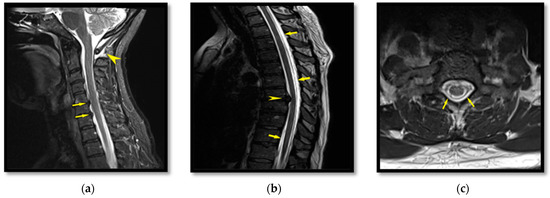

2.3. Patient III